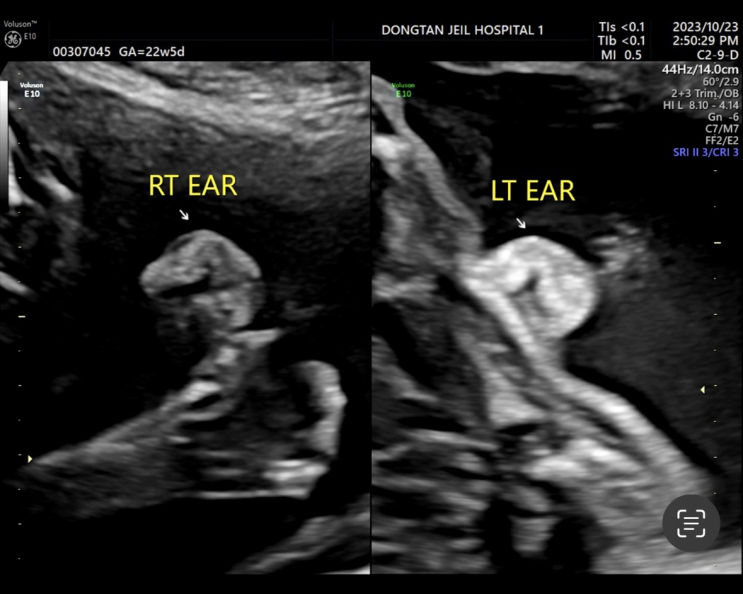

22주차 : 정밀 초음파, 초음파 잘 보는 방법, 초음파 꿀팁

22주 5일 차였던 10월 23일(월)에 정밀 초음파를 봤다. 근데 이날 처음 맞이하는 결혼기념일 이었음ㅋㅋㅋ...